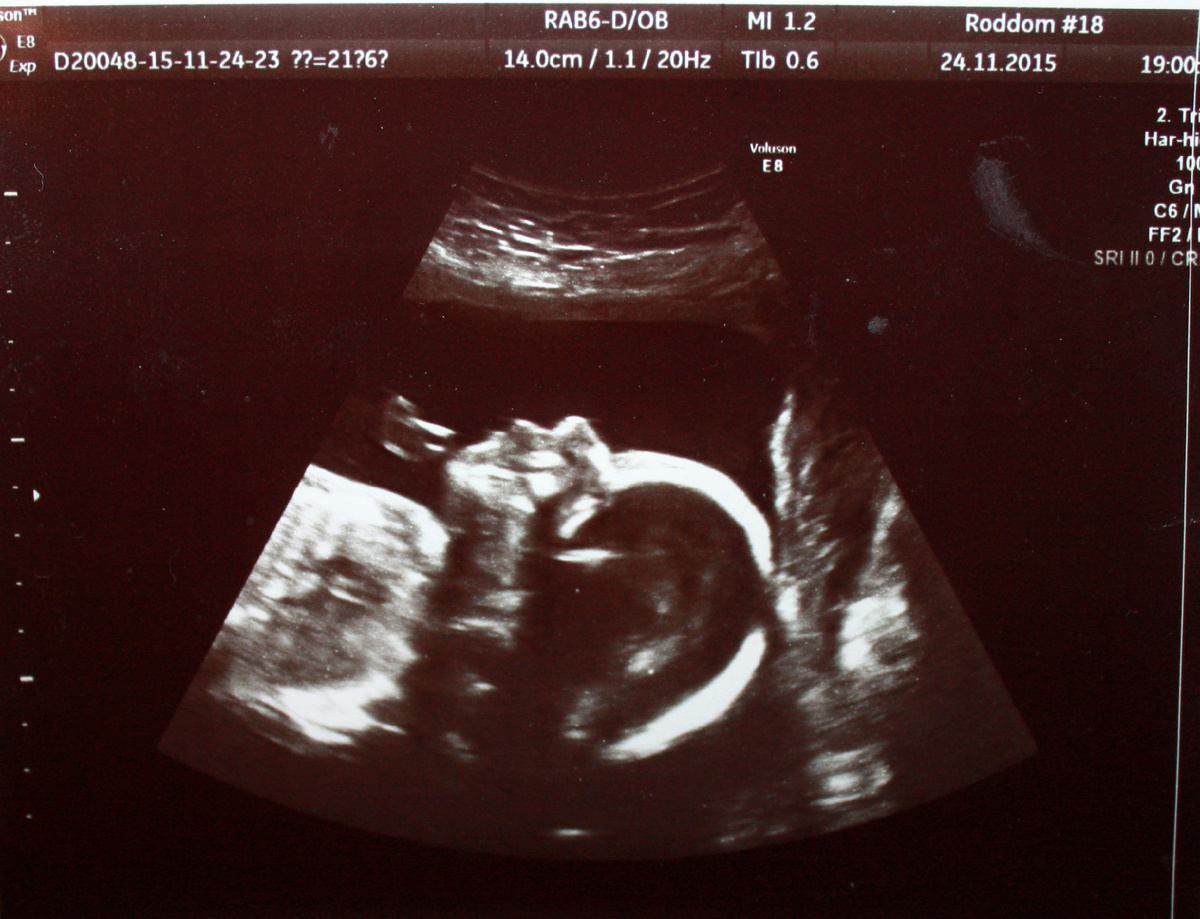

Когда до Нового года оставалось буквально два дня, перед переводом в дежурное дородовое отделение было решено провести еще одно УЗИ. –Вот подарочек кому-то на праздники достанется, – сказала, глядя в монитор, одна из врачей. Вернее, это был УЗИ-консилиум, там собралось несколько врачей, чтобы посмотреть, чего нам всем ждать в ближайшее время. Кабинет был небольшой, на стене за спиной у врача висели внутриутробные 3D-снимки малышей, несколько врачей помимо Елизаветы Валерьевны склонились над монитором и внимательно вглядывались в бездну экрана. Ситуация была, мягко говоря, не очень, и на фразу Анны Владимировны, моего лечащего врача, что по анализам все неплохо, Елизавета Валерьевна, одна из самых опытных специалистов по УЗИ, сказала: – Да что мне анализы, вы на экран посмотрите! Однако она была предельно тактична и при мне ничего пугающего не говорила, хотя по ее лицу и так было все понятно. Сейчас отслойки нет, но плацента по-прежнему низко, и, похоже, не поднимется. – Шейка укоротила

УЗИ-снимок малыша